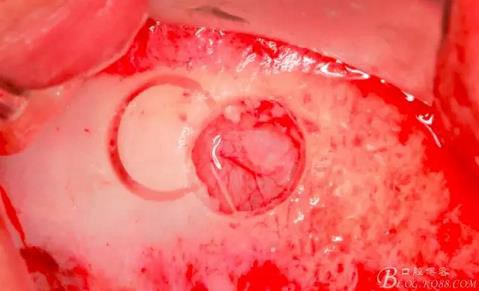

連接水壓系統(tǒng)(工具盒里的橡皮塞是無色透明的)。

用橡皮塞完全封閉洞口注入1-2mml水。

此時頰側竇膜與骨壁已經(jīng)分離,無需擔心開窗損傷竇膜。使用環(huán)切鉆以小洞口為中心開窗,轉速500轉,為了保證安全,可以將種植機調(diào)成反轉模式,一樣有強大的切割效率。